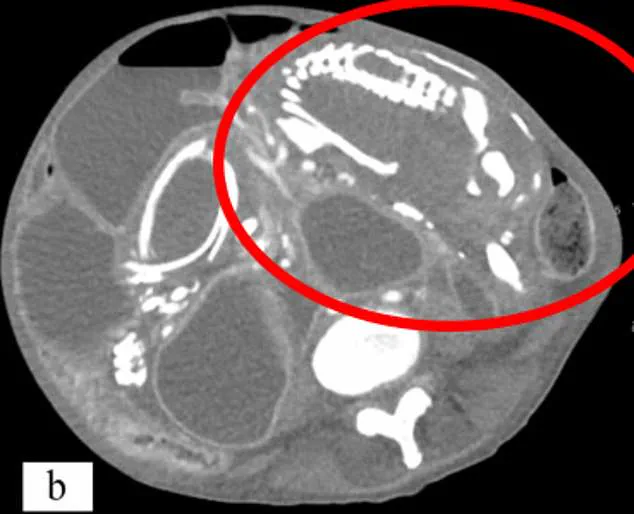

Doctors emphasize that lithopedion is an exceptionally rare consequence of an ectopic pregnancy, a condition where the fertilized egg implants outside the uterus. In such cases, the embryo fails to develop and eventually dies. When the pregnancy is less than 12 weeks, the fetus's cartilage skeleton can be reabsorbed by the body. However, if the pregnancy progresses beyond that point, the skeleton hardens into bone, making it impossible for the body to break it down. The maternal immune system then shields the dead fetus by encasing it in calcium—a process akin to mummification. This calcified mass remains in the abdomen for years unless detected and removed through medical intervention.

The medical community warns that lithopedion can remain undetected for decades, often causing no symptoms. However, when it does manifest, it may lead to chronic abdominal pain, urinary frequency, or constipation due to pressure on surrounding organs. In severe cases, the mass can become infected, leading to abscesses or life-threatening conditions. Socio-economic factors play a significant role in the prevalence of lithopedion, with limited access to healthcare and cultural stigmas often delaying diagnosis. In some cases, women may carry a lithopedion for years without knowing, only discovering it during post-mortem examinations or scans for unrelated issues.